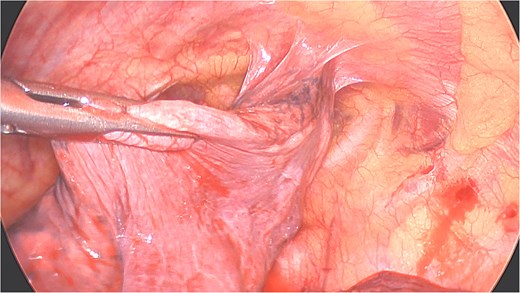

Under general anesthesia with a left double-lumen intubation a left thoracoscopy (VATS) was done using one 11 mm trocar and 2 trocars of 5 mm and a 30° 5 mm camera. We saw a pleural cavity with dense apical adhesions of the left upper lobe against the inferior border of the clavicle (Fig. 3).

Perioperative views of the migrated K-wire, showing dense apical adhesions of the left upper lobe.